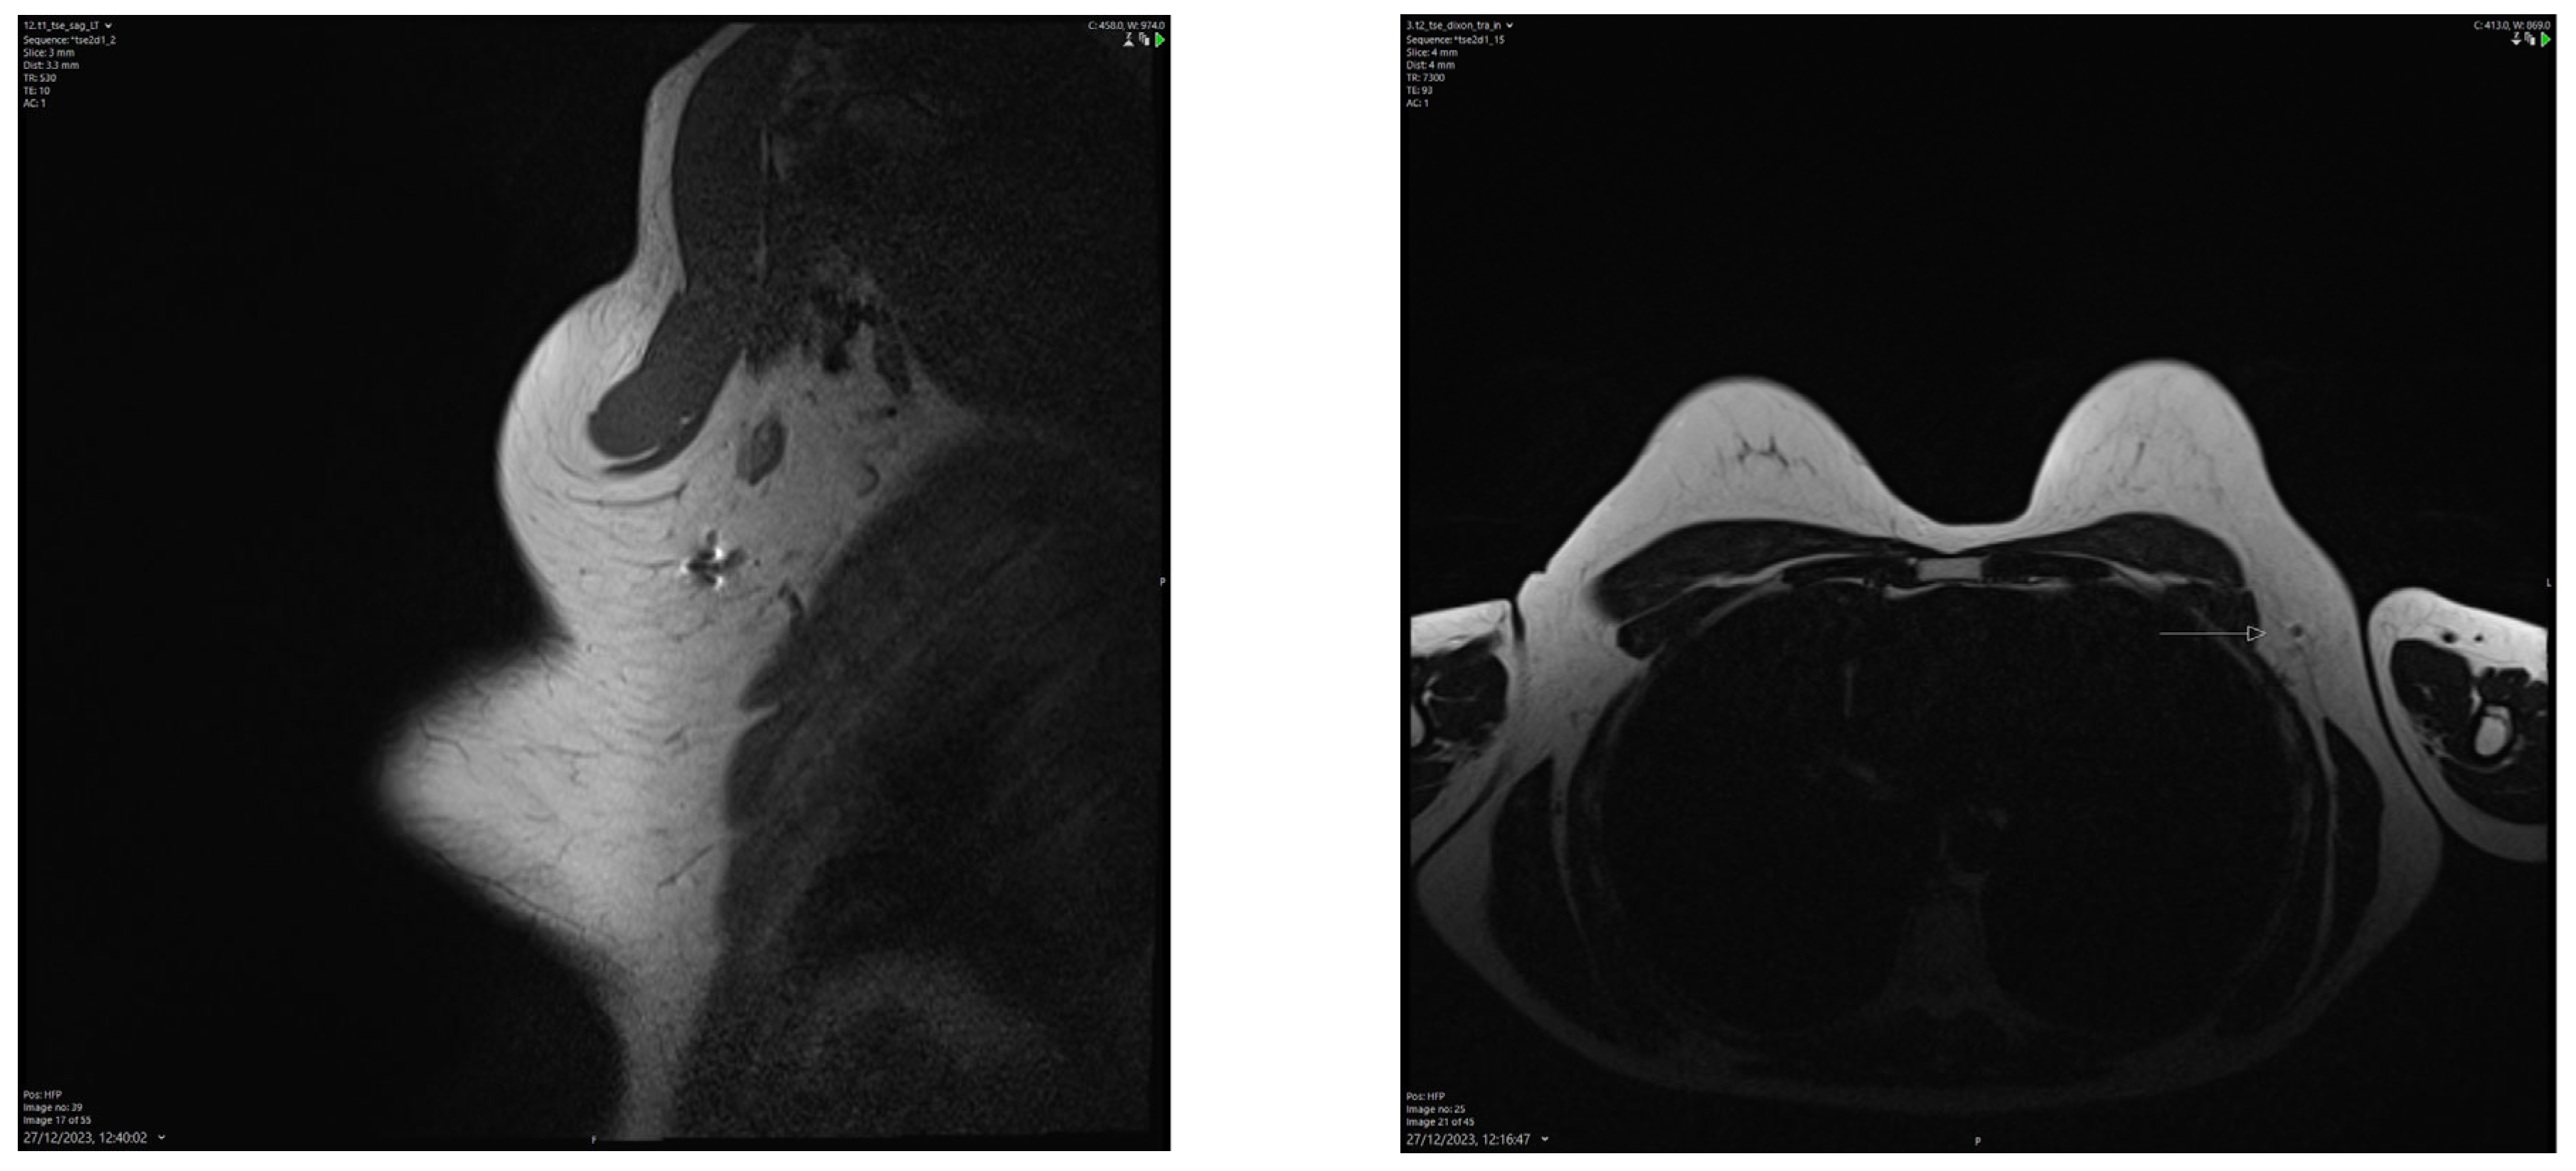

We found that the average duration between the deployment of the electromagnetic reflector and surgery ranged from 1 to 202 days, with a mean of 52 days. This observation underscores the advantages of RRL localisation, such as flexible scheduling and separating the radiological and surgical procedures. Typically, the duration of NST falls between 90 and 180 days. Hence, our findings align with the practice in some centres where target lymph nodes are tagged with clips at diagnosis and the reflector is deployed as a secondary procedure (Figure 2) leading up to the surgery date. In our centre, we typically deploy an electromagnetic reflector during the biopsy of pathological lymph nodes (Figure 3). This ensures a high precision and accurate tagging, thereby saving time and resources by eliminating the need for a second localisation procedure. This practice is supported by the fact that the SAVI SCOUT® reflector is known for its resistance to migration and inactivation over a long period of time [8,9,10,17]. Using Magseed® (Endomagnetics Inc., Cambridge, UK) to facilitate TAD, Barry et al. reported that Magseeds® inserted to localise tagged lymph nodes after the completion of NST were found outside the node in neighbouring axillary tissues in 24.3% of cases, compared to 1.8% when Magseeds® were placed upon the commencement of NST [25]. However, the high incidence (24.3%) of the malpositioning of magnetic seeds reported by Barry et al. after NST has not been corroborated by other investigators.

Figure 2. A secondary Scout localisation of a previously tagged lymph node. Reflector indicated by blue arrow. Previously included in our previous publication [7].

Figure 3. A primary Scout localisation at the time of biopsy. Reflector indicated by blue arrow. Previously included in our previous publication [7].